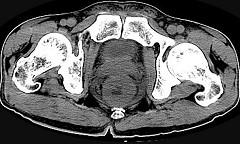

问题 男,56岁,排便形状改变,便不尽感,CT检查如图所示,下列说法正确的是 ( )

选项 A.肠壁上有蒂状新生物 B.其表面光滑,边界清楚 C.肠腔未见狭窄 D.此为直肠息肉 E.此为直肠癌

答案 E